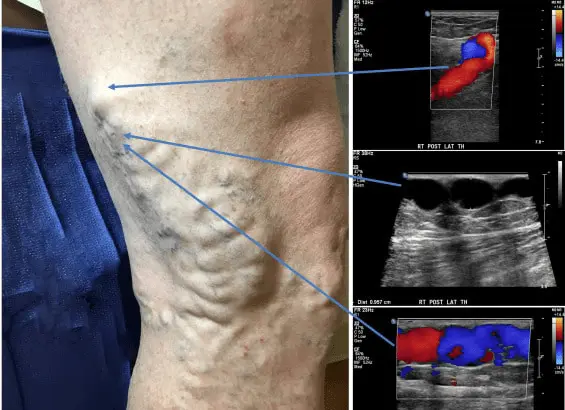

دکتر بهنام واقفی یکی از جراحان بسیار با تجربه در زمینه واریس و قلب می باشند که در کلینیک فوق تخصصی خود با استفاده از به روزترین و مجهزترین دستگاه ها و روش های نوین به درمان بیماران می پردازند.